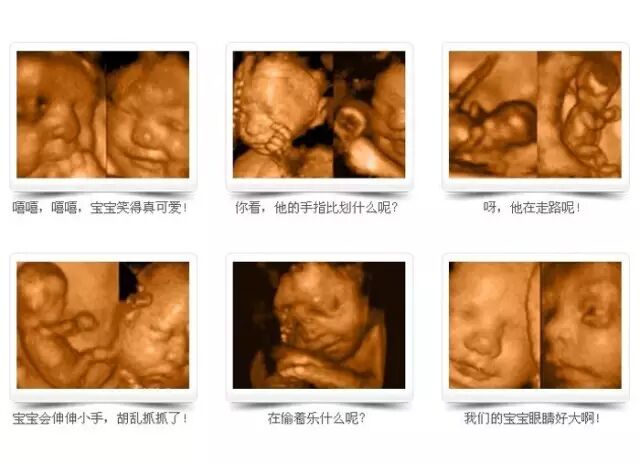

四维彩超不再是仅仅感觉宝宝的呼吸和运动,而是可以亲眼目睹他们的一举一动和乖巧的秀容。更为重要的是,四维彩超能够多方位、多角度地观察宫内胎儿的生长发育情况,为早期诊断胎儿先天性体表畸形和先天性心脏疾病提供准确的科学依据。